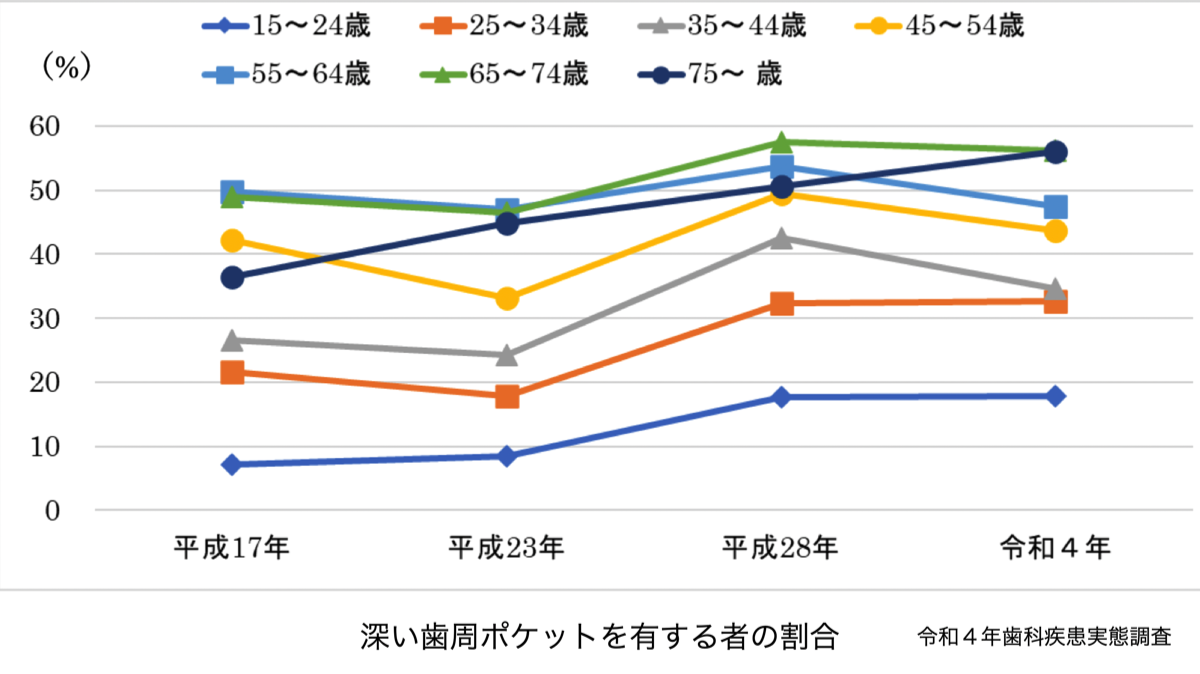

令和4年の歯科疾患実態調査を見ても、加齢にしたがい歯周炎を持つ人の割合が増えています。一方、口腔衛生も普及して歯のクリーニングに歯科医院を受診する人が増加しているにもかかわらず、歯周炎を持つ人の割合が、55-64歳を除いた各年齢層で増加の一途でした。

令和4年の歯科疾患実態調査を見ても、加齢にしたがい歯周炎を持つ人の割合が増えています。一方、口腔衛生も普及して歯のクリーニングに歯科医院を受診する人が増加しているにもかかわらず、歯周炎を持つ人の割合が、55-64歳を除いた各年齢層で増加の一途でした。